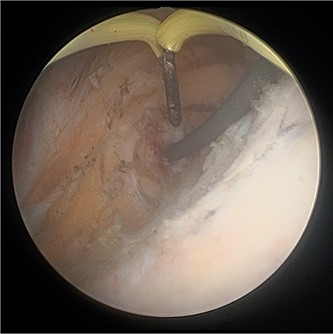

On both cases, under general or regional anaesthesia, a cystoscopy was performed and the interureteric bar was identified. A hybrid ‘sensor’ or ‘Terumo’ hydrophilic guidewire was advanced concurrently using the access from the existing nephrostomy tube with fluoroscopic assistance down to the level of the ureteric cul-de-sac. A combined visual- and x-ray-guided approach verified the exact location of the course of the intramural ureter, in correlation to the resectoscope and a Collins knife was used to incise the bladder mucosa (Fig. 2) above the level of the guidewire, on the virtual course of the intramural ureter exposing the intramural ureter. In all three attempts, the incision of bladder mucosa above the antegrade ureteric guidewire ended up with a successful identification of the guidewire, allowing access to the ureteric cul-de-sac. Stent graspers were used to snare the guidewire into the bladder (Fig. 3). With safety wire in place, management of the neo-orifice could then be performed.

Cystoscopic view of exposed left VUJ with identification of terumo guidewire passed antegradely.